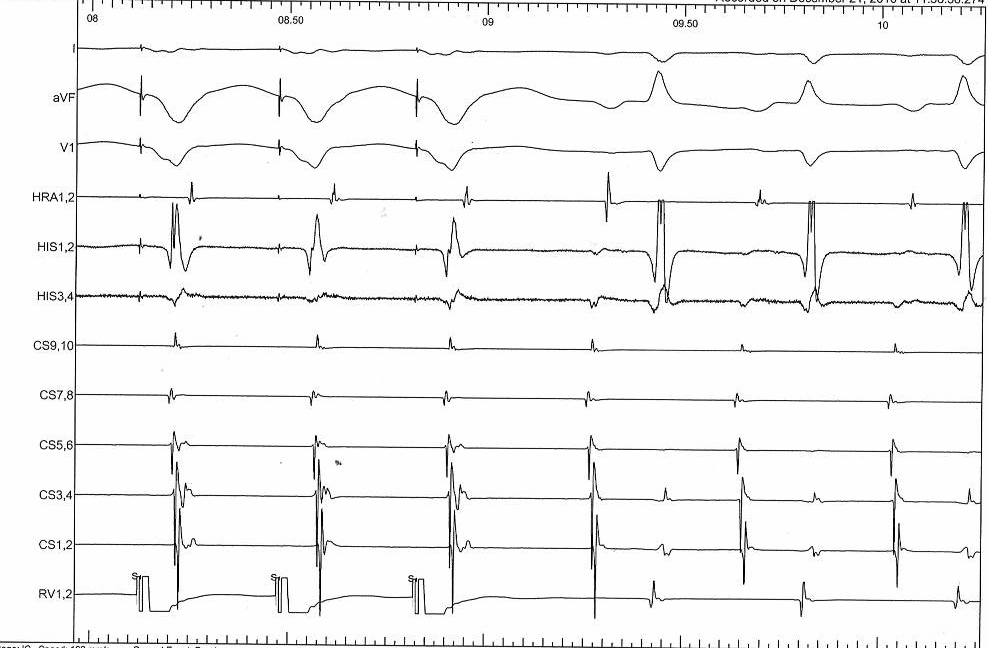

RV pacing in AT - VAAV

VAAV.jpg

• VAAV - AT

• VAV - AVNRT

• Sequence - VAV or VAAV

Response

• Atrium not entrained - AT / AVNRT